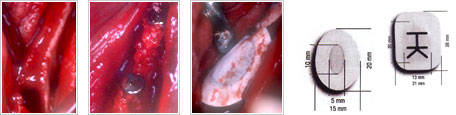

①

抜歯後の状態です。

何も処置しない場合は3~5mm

幅がなくなります。

②

骨充填剤です。

③

抜歯窩に(根のあった穴に)

②の骨粉を入れます。

④

抜歯創用保護剤(コラーゲン

使用の創面保護及び内芽

形成のためのもの)です。

⑤

③の上に入れます。

⑥

縫合したら終了です。